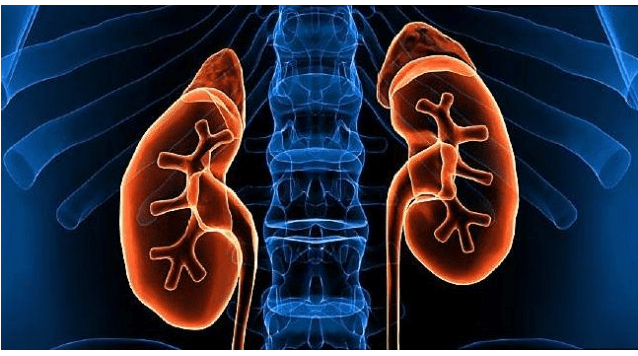

“U desh shumë kohë që truri të funksiononte sërish”, Eminem flet për momentin që desh humbi jetën

By

Aida Topalli